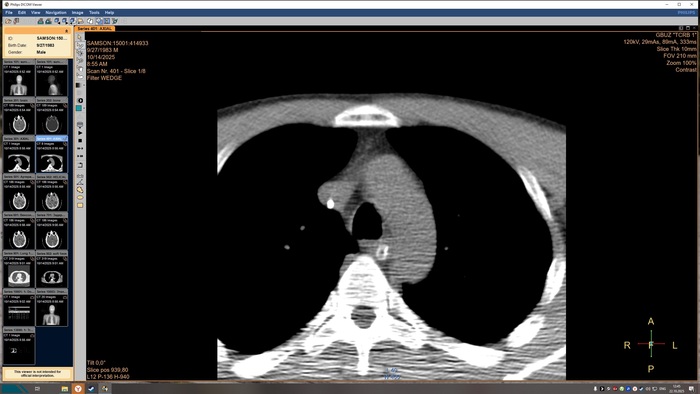

Описание КТ прикрепляю, а снимки будут в конце поста, по-другому у меня не получилось.

На топограмме, серии аксиальных срезов и реконструкций получены изображения суб- и

супратенториальных структур головного мозга от большого затылочного отверстия до крыши

черепа в нативном виде и в/в контрастированием. Определяются: справа четко

идентифицируемые внутричерепные интрапаренхиматозные гиперденсные неоднородные

очаги, копящее контрастное вещество, плотностью до 51-55ед.Х., размером: в проекции

лучистого венца 8х8х9 мм, в проекции продолговатого мозга 21х26х19 мм, Срединные

структуры мозга не смещены. Боковые желудочки: правый до 10,2 мм, левый до 12,9 мм,

третий-2,6 мм, четвёртый-13,8 мм. Селлярная и хиазмальная области без видимых

патологических изменений. Цистерны основания мозга, конвекситальные ликворные

пространства и борозды полушарий большого мозга сужены. Оболочки мозга без

особенностей. Миндалины мозжечка расположены соответственно возрасту. Дополнительных

образований и жидкостных скоплений в воздухоносных полостях височных костей с обеих

сторон, полости носа и его придаточных пазух не выявлено. Содержимое глазниц

визуализируется без особенностей. Признаков остеолитического, -пластического процессов,

аномалий развития и/или травматических повреждений костей черепа исследованного уровня

не выявлено. На прямой топограмме, серии аксиальных срезов и реконструкций получены

изображения органов грудной клетки от уровня верхней апертуры грудной клетки до уровня

задних рёберно-диафрагмальных синусов в нативном виде. Легкие в полном объёме,

пневматизация снижена. Справа в С3 выявляется бронхопневмоническая инфильтрация.

Конфигурация и просвет стволовых бронхов сохранены. Средостение обычной формы и

положения, дополнительных образований в нём не выявлено. Внутригрудные

бифуркационные и парааортальные лимфатические узлы не увеличены. Анатомия крупных

сосудов не нарушена, размеры в пределах нормы, стенки аорты и венечных артерий с очагами

кальцинатов. Плевральные утолщения и скопления жидкости отсутствуют. Диафрагма и мягкие

ткани грудной клетки без видимых патологических изменений. Признаков остеолитического, -

пластического процессов, травматических повреждений костных структур на исследованном

уровне не выявлено. ДИ по типу остеохондроза.

Заключение

КТ-признаки очаговых образований головного мозга. КТ-признаки правосторонней

верхнедолевой сегментарной б/пневмонии. ДИ ГОП.

Снимки КТ